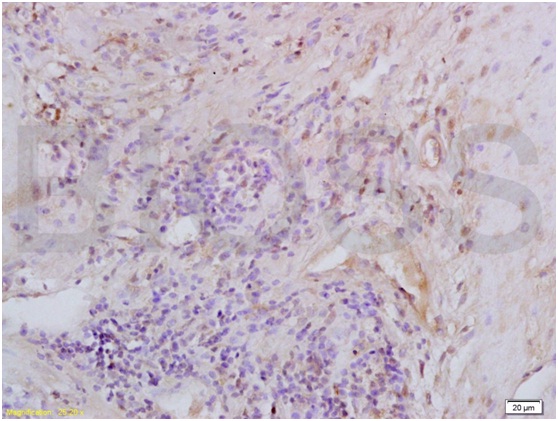

Antigen retrieval: citrate buffer ( 0.01M, pH 6.0 ), Boiling bathing for 15min; Block endogenous peroxidase by 3% Hydrogen peroxide for 30min; Blocking buffer (normal goat serum,C-0005) at 37℃ for 20 min;

Incubation: Anti-MIP2/GRO Beta/CXCL2 Polyclonal Antibody, Unconjugated(bs-1162R) 1:200, overnight at 4℃, followed by conjugation to the secondary antibody(SP-0023) and DAB(C-0010) staining